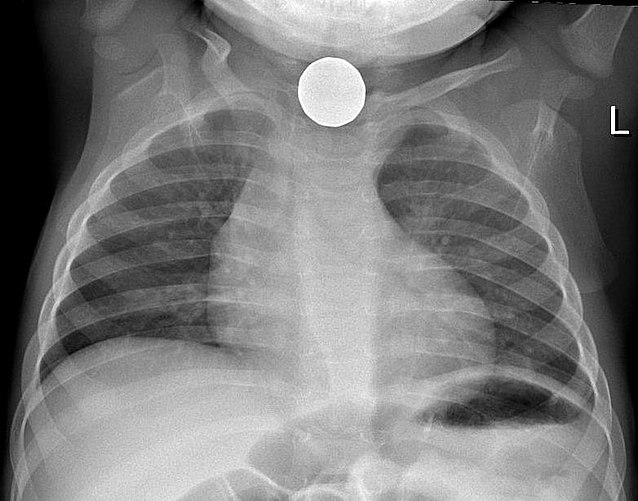

2: 버튼 배터리

• 이 중 버튼 배터리는 삼킨 지 3~4시간 내 식도 전 층에 화상을 유발할 수 있어 최대한 빨리 내시경적으로 제거해야 한다.